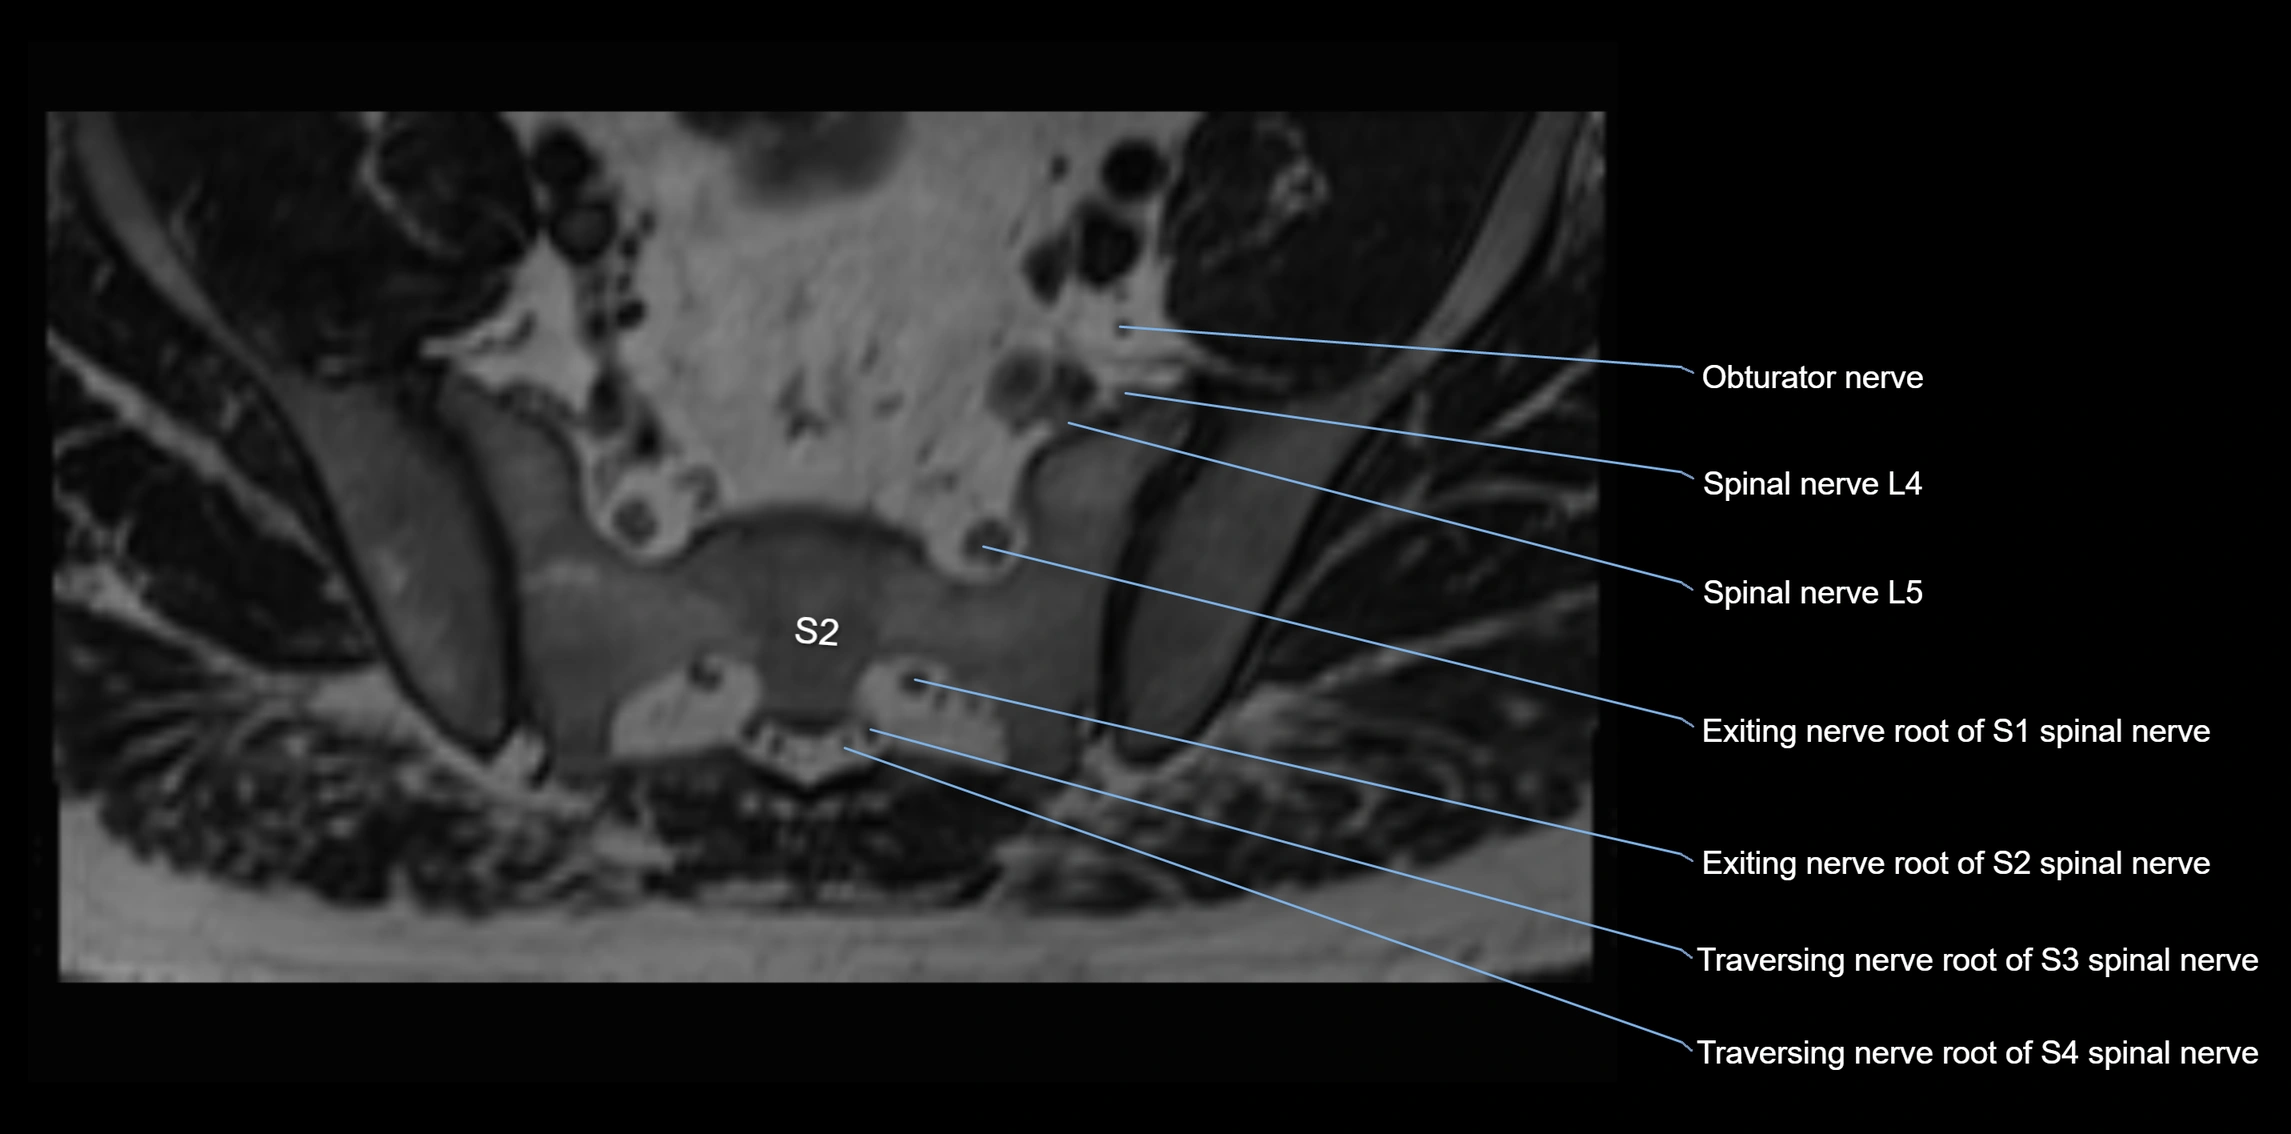

MRI Appearance

T1-weighted images:

• Nerve appears as a very thin low-to-intermediate signal intensity structure

• Surrounded by bright fat, aiding visualization

T2-weighted images:

• Nerve shows intermediate to mildly hyperintense signal compared to muscle

• Pathological involvement appears brighter

STIR (Short Tau Inversion Recovery):

• Normal nerve appears dark

• Inflamed or entrapped nerve appears bright hyperintense

T1 Fat-Sat Post-Contrast:

• Normal nerve enhances minimally

• Pathologic nerve (neuritis, entrapment, tumor infiltration) shows focal or diffuse enhancement

3D T2 SPACE / CISS:

• Nerve appears intermediate to mildly hyperintense compared to muscle

• Surrounded by bright fat or CSF, improving visualization

• Best sequence for mapping small pelvic nerves such as the anococcygeal